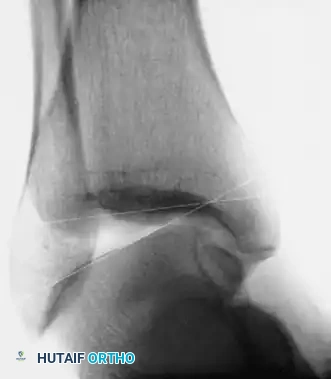

- Stress Radiography: Mechanical instability is confirmed when stress radiographs demonstrate 8 to 10 degrees of increased talar tilt in the ankle mortise compared with the contralateral normal ankle.

- Advanced Imaging: If stress radiographs are negative but pain persists, other etiologies such as stress fractures, osteochondral lesions of the talus (OCDs), or peroneal tendinopathy must be ruled out.